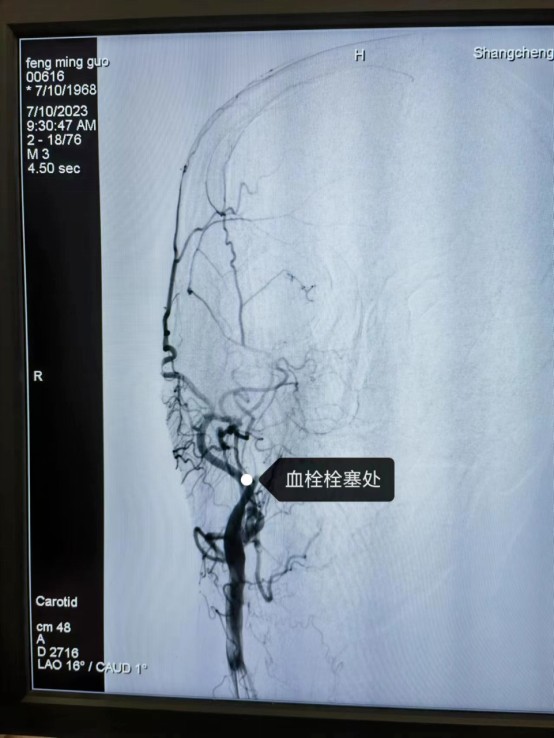

近日,55岁的冯先生突发急性脑梗死,我院卒中中心启动绿色通道,给予静脉溶栓桥接取栓治疗,成功打通堵塞的“生命管道”,患者转危为安,术后恢复良好,避免了“一人中风,全家瘫痪”的悲剧。